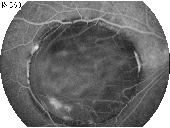

349 350 351 352